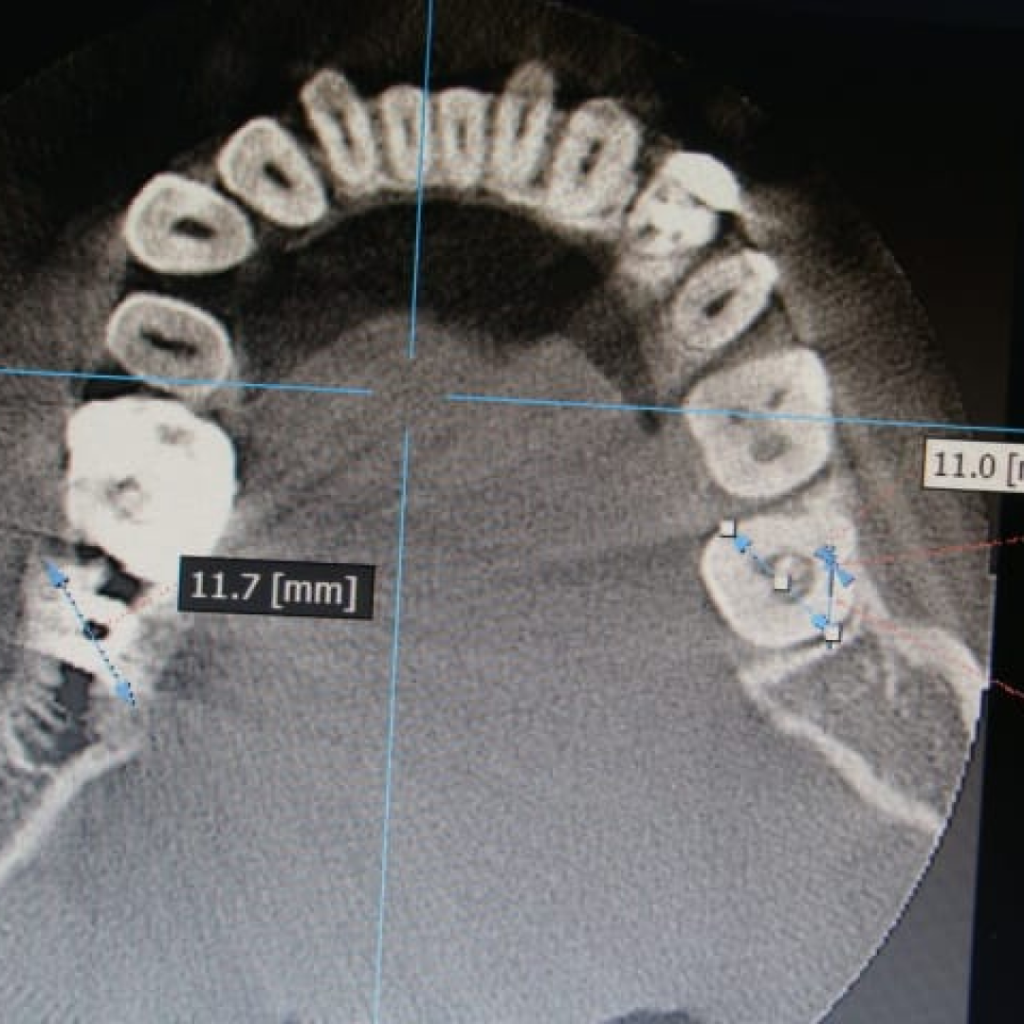

- диаметр лунок более 11 мм

- Установка имплантата AnyRidge (Ø 8,0 мм, h 10,0), с торком 50-55 (данные ISQ 62-66)